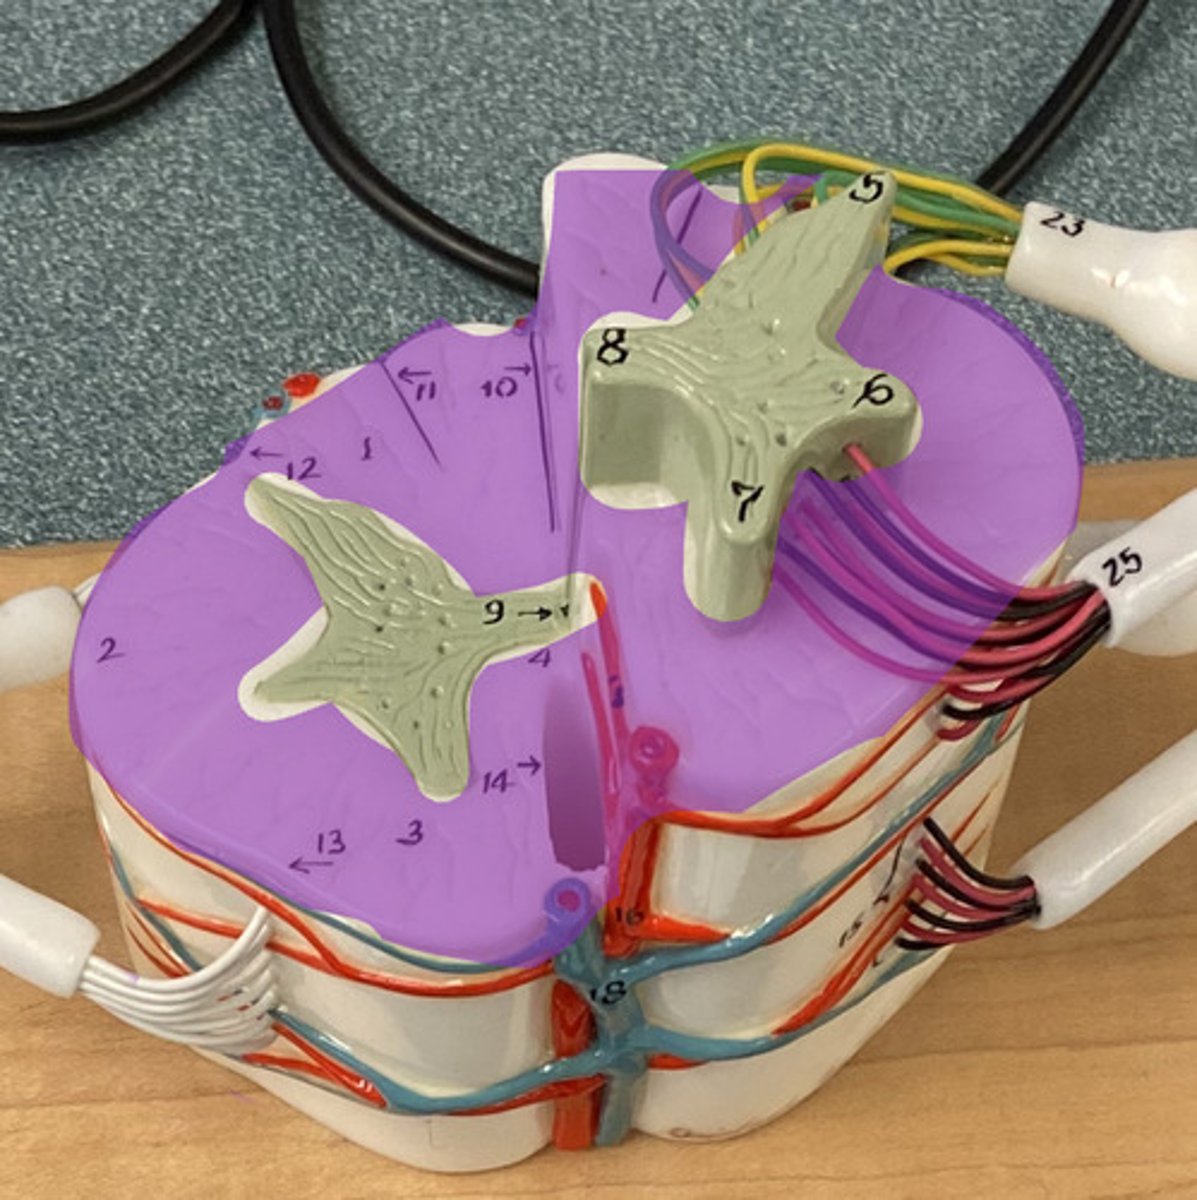

White Columns/ Matter

Gray Matter

Dorsal Horn

Lateral Horn

Dorsal (posterior) Median Sulcus

Ventral (anterior) Median Fissure

Central Canal

Ventral Root

Dorsal Root

Dorsal Root Ganglion